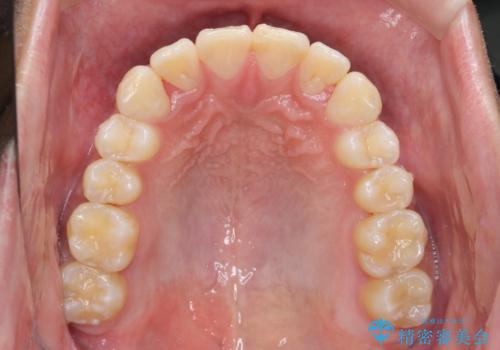

遠心移動を伴うマウスピース非抜歯矯正治療

- 「前歯の見た目を改善したい。」と矯正治療を希望され来院されました。

前歯のガタつきに加え、上顎が前にある咬合関係(上顎前突)を改善すべく、マイクロインプラントを用いた上顎奥歯の後方移動、拡大、ディスキングを用いたマウスピース矯正治療を計画します。

マイクロインプラントを使用したことで、しっかりと遠心移動が為され、良好な咬合関係が達成されました。